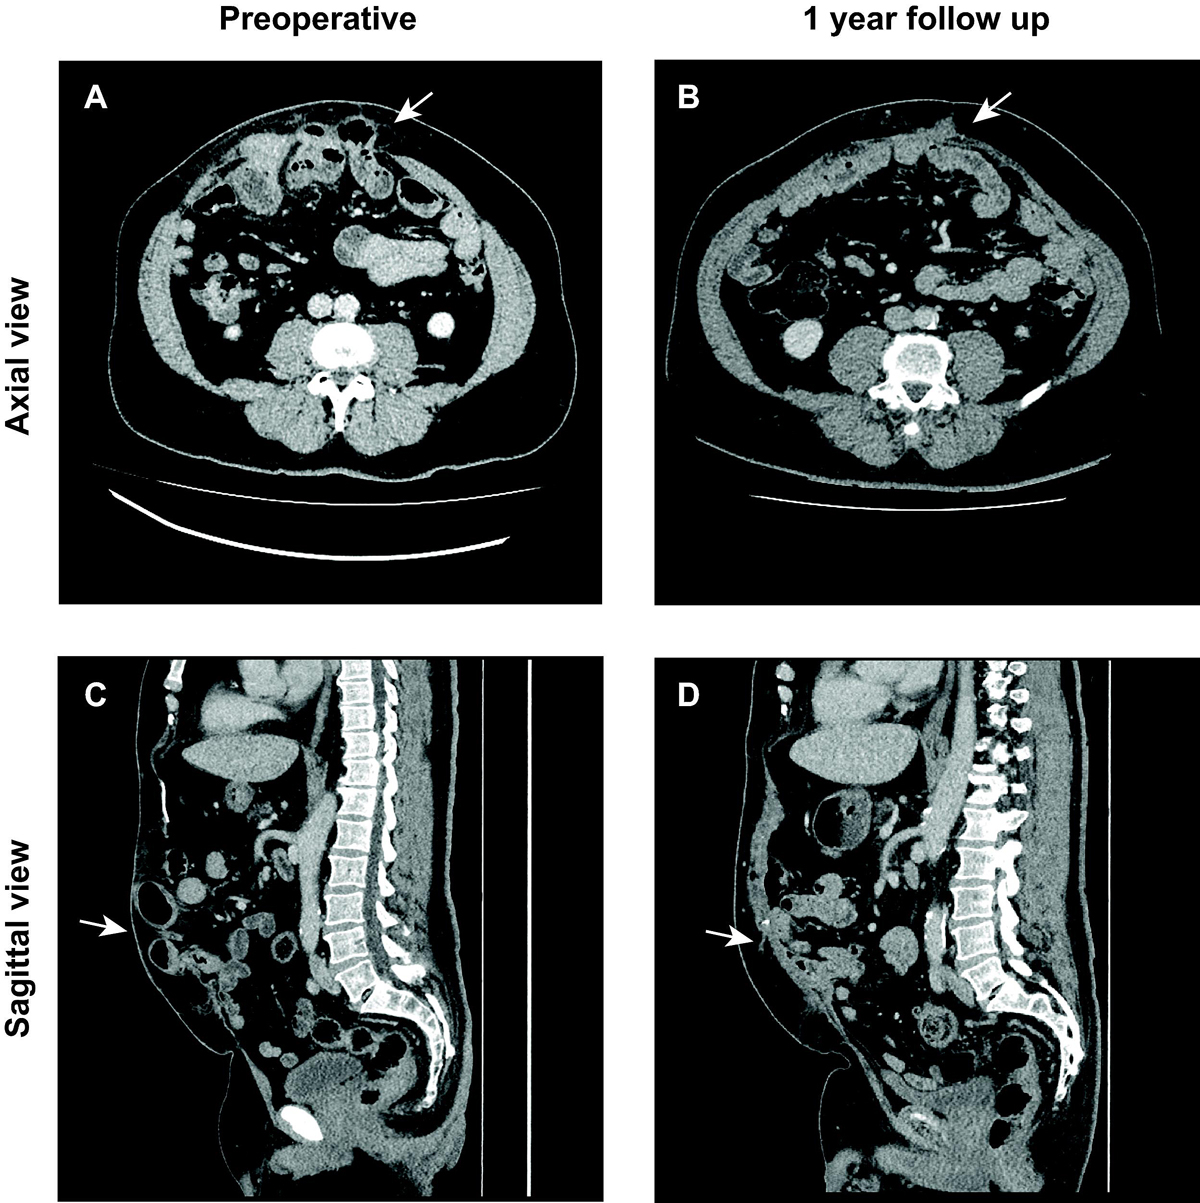

His blood tests on presentation did not show a significant inflammatory syndrome, with a leucocyte count of 10 G/l and C-reactive protein level of 74 mg/l. Abdominal computed tomography showed a supra-umbilical incisional hernia with multiple defects of the abdominal wall associated with a strangulated hernia of the small intestine at the site of previous stoma, with signs of tissue damage (fig 1a,c). Following this finding, a nasogastric tube was inserted under smooth suction and the patient was admitted to the operating room for an emergency laparoscopic eTEP. This technique was indicated in this patient’s case because of the presence of multiple abdominal wall defects and in order to avoid the longer hospital stay and postoperative complications that might follow an open approach. The patient was placed in the French position under general anaesthesia. The strangulated hernia was reduced before incision after anaesthesia induction. Trocars were inserted into the left lower quadrant and an explorative laparoscopy was performed, which showed a total absence of intestinal ischaemia and widespread adhesions that required extensive adhesiolysis. After total adhesiolysis, the left preperitoneal retrorectus space was dissected, then crossover to the contralateral retrorectus space permitted the creation of operative space from the xiphoid to the pubis. Because tension on the posterior wall prevented closure, TAR was performed. There was a significant diastasis of the rectus abdominis, with a defect of 10 × 15 cm, as well as another 6 × 4 cm defect near the upper right quadrant. The posterior wall was closed and a 30 × 30 cm Versatex mesh was deployed without fixation. The operating time was around 6 hours.

Figure 1 Abdominal computed tomography (CT) scan of the strangulated hernia in axial (a) and sagittal (c) views. Abdominal CT at 1-year follow up in axial (b) and the sagittal (d) views.

No drain was placed during the procedure and the patient remained hospitalised for 5 days, where the immediate postoperative period was uncomplicated. However, at the 30th post-operative day, there was a symptomatic seroma causing pain in the surgical site, which needed surgical evacuation, but was completely resolved at 1-year follow-up with no symptoms at all (fig.1b,d). Bacteriological culture of the seroma was negative.